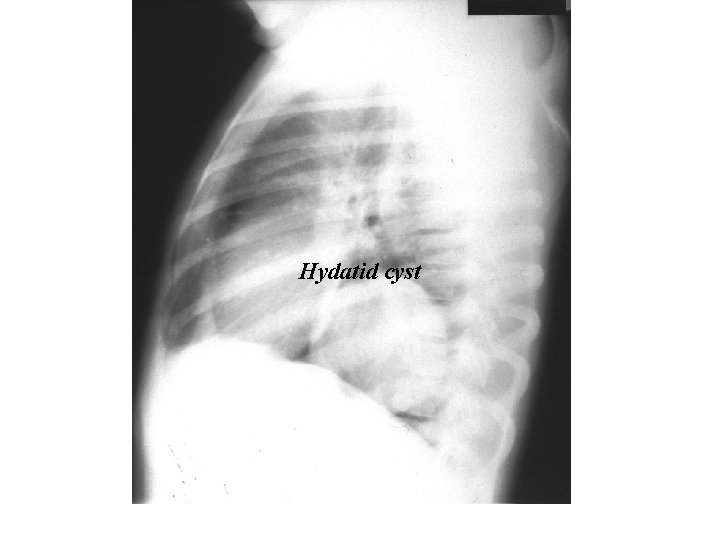

Hydatid cyst